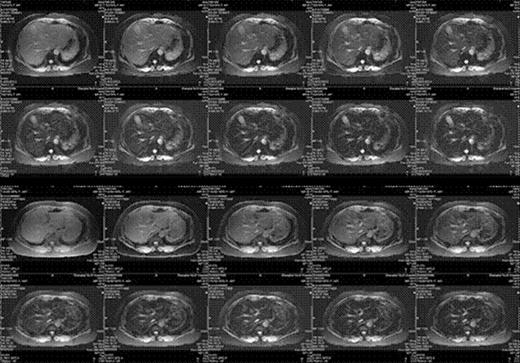

Results: LPI has a statistical difference (P<0.001 by ANOVA), which decreased gradually, among three groups, while no difference was found in ASF (P=0.086 by ANOVA). After DFO treatment, serum hepcidin expression increased from 301.26±59.78¦Ìg/L to 340.33±49.78¦Ìg/L (P=0.032), while hepcidin/ASF was up-regulated gradually from 0.16±0.08 to 0.22±0.03 (P=0.045). APAF-1 expression (P=0.047) and erythroid apoptosis rate (P=0.009) decreased significantly, respectively. No statistical difference was found in EPO (P=0.247) and GDF15 expression (P=0.172). LIC dropped from 9.83±4.84mg/g dry weight to 6.28±4.01mg/g dry weight (P<0.001). No significant difference was found in cardiac T2* (P=0.594). LPI has a closer connection to LIC than ASF (r=0.739, P<0.001 vs. r=0.321, P=0.034). (Figure1)

Before DFO treatment, a patient had an abnormal liver function. Along with iron chelation therapy, his LPI decreased rapidly. Meanwhile, his ALT dropped and his hemoglobin increased gradually. Furthmore, his LIC decreased after receiving DFO treatment.

Lane a: LIC was 9.97mg/g dry weight on week 0.

Lane b: LIC was 5.81mg/g dry weight on week 26.

The improvement of ALT, hemoglobin and LIC